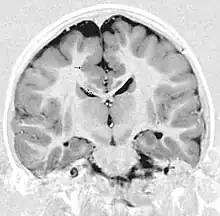

| This child presented with seizures. The coronal true inversion recovery sequence shows thickened and disordered cortex in superior frontal and cingulate gyri bilaterally (arrow). There are small convolutions visible at the corticomedullary junction. The appearance is that of cortical dysplasia, with polymicrogyria more likely than pachygyria due to the small convolutions visible. There are also small foci of grey matter signal in the corpus callosum, deep to the dysplastic cortex (double arrows). These probably represent areas of grey matter heterotopia. | |

Pathologically, PMG is defined as "an abnormally thick cortex formed by the piling upon each other of many small gyri with a fused surface."[14] To view these microscopic characteristics, magnetic resonance imaging (MRI) is used. First physicians must distinguish between polymicrogyria and pachygyria. Pachygria leads to the development of broad and flat regions in the cortical area, whereas the effect of PMG is the formation of multiple small gyri. Underneath a computerized tomography (CT scan) scan, these both appear similar in that the cerebral cortex appears thickened. However, MRI with a T1 weighted inversion recovery will illustrate the gray-white junction that is characterized by patients with PMG.[13] An MRI is also usually preferred over the CT scan because it has sub-millimeter resolution. The resolution displays the multiple folds within the cortical area, which is continuous with the neuropathology of an infected patient.